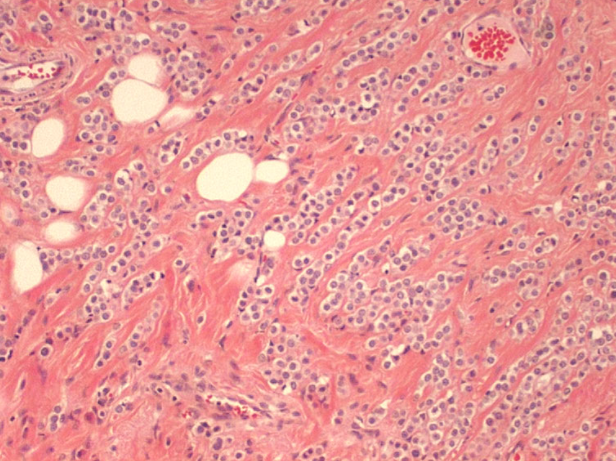

What type of breast cancer is shown?

Mucinous carcinoma